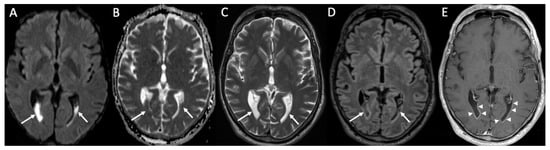

| West Nile virus | • Hyperintensity in T2 and FLAIR of basal ganglia, thalami and midbrain |

| Enterovirus | • Rhombencephalitis |